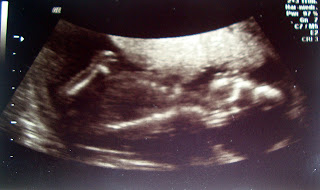

Letzte Woche war ich bei meinem Lieblings-Onkel-Doktor: meinem Frauenarzt. Ich liebe es dort hinzugehen und dann zu hören, dass alles super ist. Ich liebe es auch, dieses kleine Etwas via Ultraschall zappeln zu sehen und freue mich, dass es immer mehr nach Baby aussieht. (Auch, wenn man dass auf dem Bild eventuell nicht sieht)

Mein FA hat dann diesmal das Geschlecht erkennen können und war sich sicher, dass wir eine Tochter bekommen. Ich bin sehr begeistert. Erst einen Jungen und nun ein Mädchen!

Laut FA ist die kleine Maus zeitgerecht und das bedeutet, dass meine Tochter vielleicht an meinem Geburtstag zu Welt kommt. Ich bin sehr gespannt!!!!!!